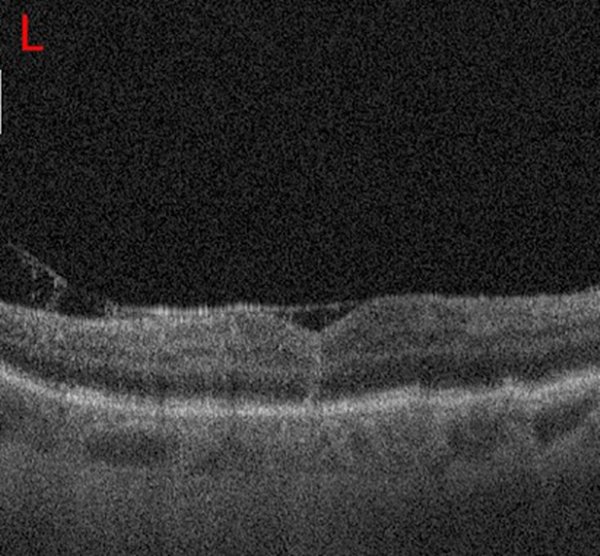

Se realizó tomografía de coherencia óptica (OCT) en OI con equipo Spectral Domain OCT Copernicus (Optopol Technology, Zawiercie, Polonia) que verificó la presencia de AM en estadio II, con un diámetro de 209 μm, sin edema ni eversión de los bordes del agujero (fig. 1).

Figura 1. La OCT prequirúrgica de mácula izquierda muestra la presencia de un agujero macular de espesor completo en estadio II, con espacio quístico intrarretinal en el margen del orificio al agujero.

A los 14 días de dicha cirugía se vuelve a reintervenir el OI por falta de cierre del AM (fig. 2).

Figura 2. Mediante OCT se observa la falta de coalescencia de los bordes luego de 7 días de la intervención quirúrgica en el AM del OI.